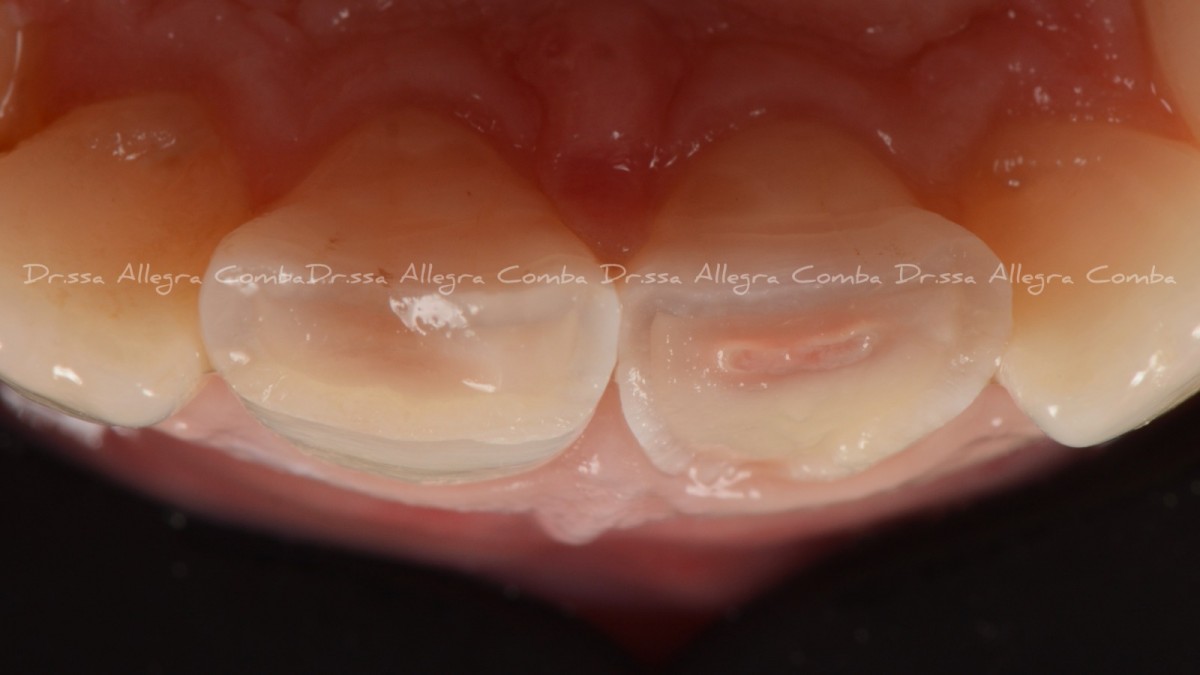

A 24-year-old male patient came to my attention reporting sensibility related to sweet and cold on the 3rd quadrant. The general medical history revealed nothing relevant.

Clinical examination highlighted old direct restorations on 3.7 and 3.6, with irregular margins and initial signs of infiltration. Rx examination (orthopantomography and bitewings) revealed primary interproximal decays with dentinal involvement on 3.4, 3.5, 3.6 and 3.7. Vitality test was carried out and confirmed that all elements were vital.

According to the fact that the patient was young and all the teeth had a sufficient quantity of sound tissue structure, a minimally invasive approach with direct restorations was proposed.

Oral hygiene motivation was carried out, alongside with proper periodontal treatment (scaling, polishing) before taking initial photo (Fig.1). Initial rx bitewing of the quadrant (Fig.2).